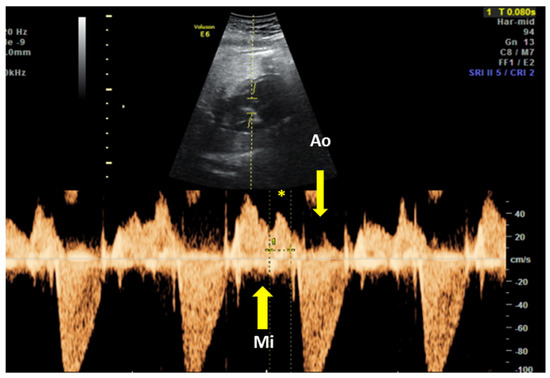

The fetal mechanical PR interval can be obtained during ultrasound examination of the fetal heart. It is recorded with the help of pulsed wave (PW) Doppler– the two-dimensional PW gate is set to 3–4 mm depending on the gestational age and placed distal to the mitral valve as such to include the origin of the left ventricle outflow tract at an angle of around 20°. With this approach, we will record spectral Doppler wave forms for both blood flows, in the mitral valve and aortic origin during a full cardiac cycle. The speed of image acquisition should be slowed (to 4–5 cm/s) in order to have a good representation of each waveform. During a normal cardiac cycle, the passive filling of the atria during generalized diastole (E wave), the active filling of ventricles during atrial systole (A wave) and blood ejection in the root of the aorta during ventricular systole will be documented (see Figure 4). The PR interval is the interval measured between the onset of atrial systole (mitral valve A-wave) and the beginning of the aortic valve flow. Normal ranges during pregnancy depend on the gestational age, fetal heart rate and sex of the baby. These correlations have been studied prospectively by A. Wojakowski et al. [78]. A mean of 122.4 ms ± SD 10.3 ms is considered normal.

Figure 4.

Pulsed wave Doppler trace used for mechanical PR interval measurement. Mi—transmitral flow (thick yellow arrow); Ao—transaortic flow (thin yellow arrow); (*)—normal PR interval—120 msec (between thin dotted yellow lines). Courtesy of Anca Panaitescu, Filantropia Clinical Hospital, Bucharest.

In a prospective trial of dexamethasone to prevent CHB progression in women with anti-Ro by Friedman et al. the definition of “abnormal” fetal Doppler mechanical PR interval was set a priori at three SD above the normal mean, to 150 ms [79]. However, none of the conduction measurements could predict the occurrence of CHB.